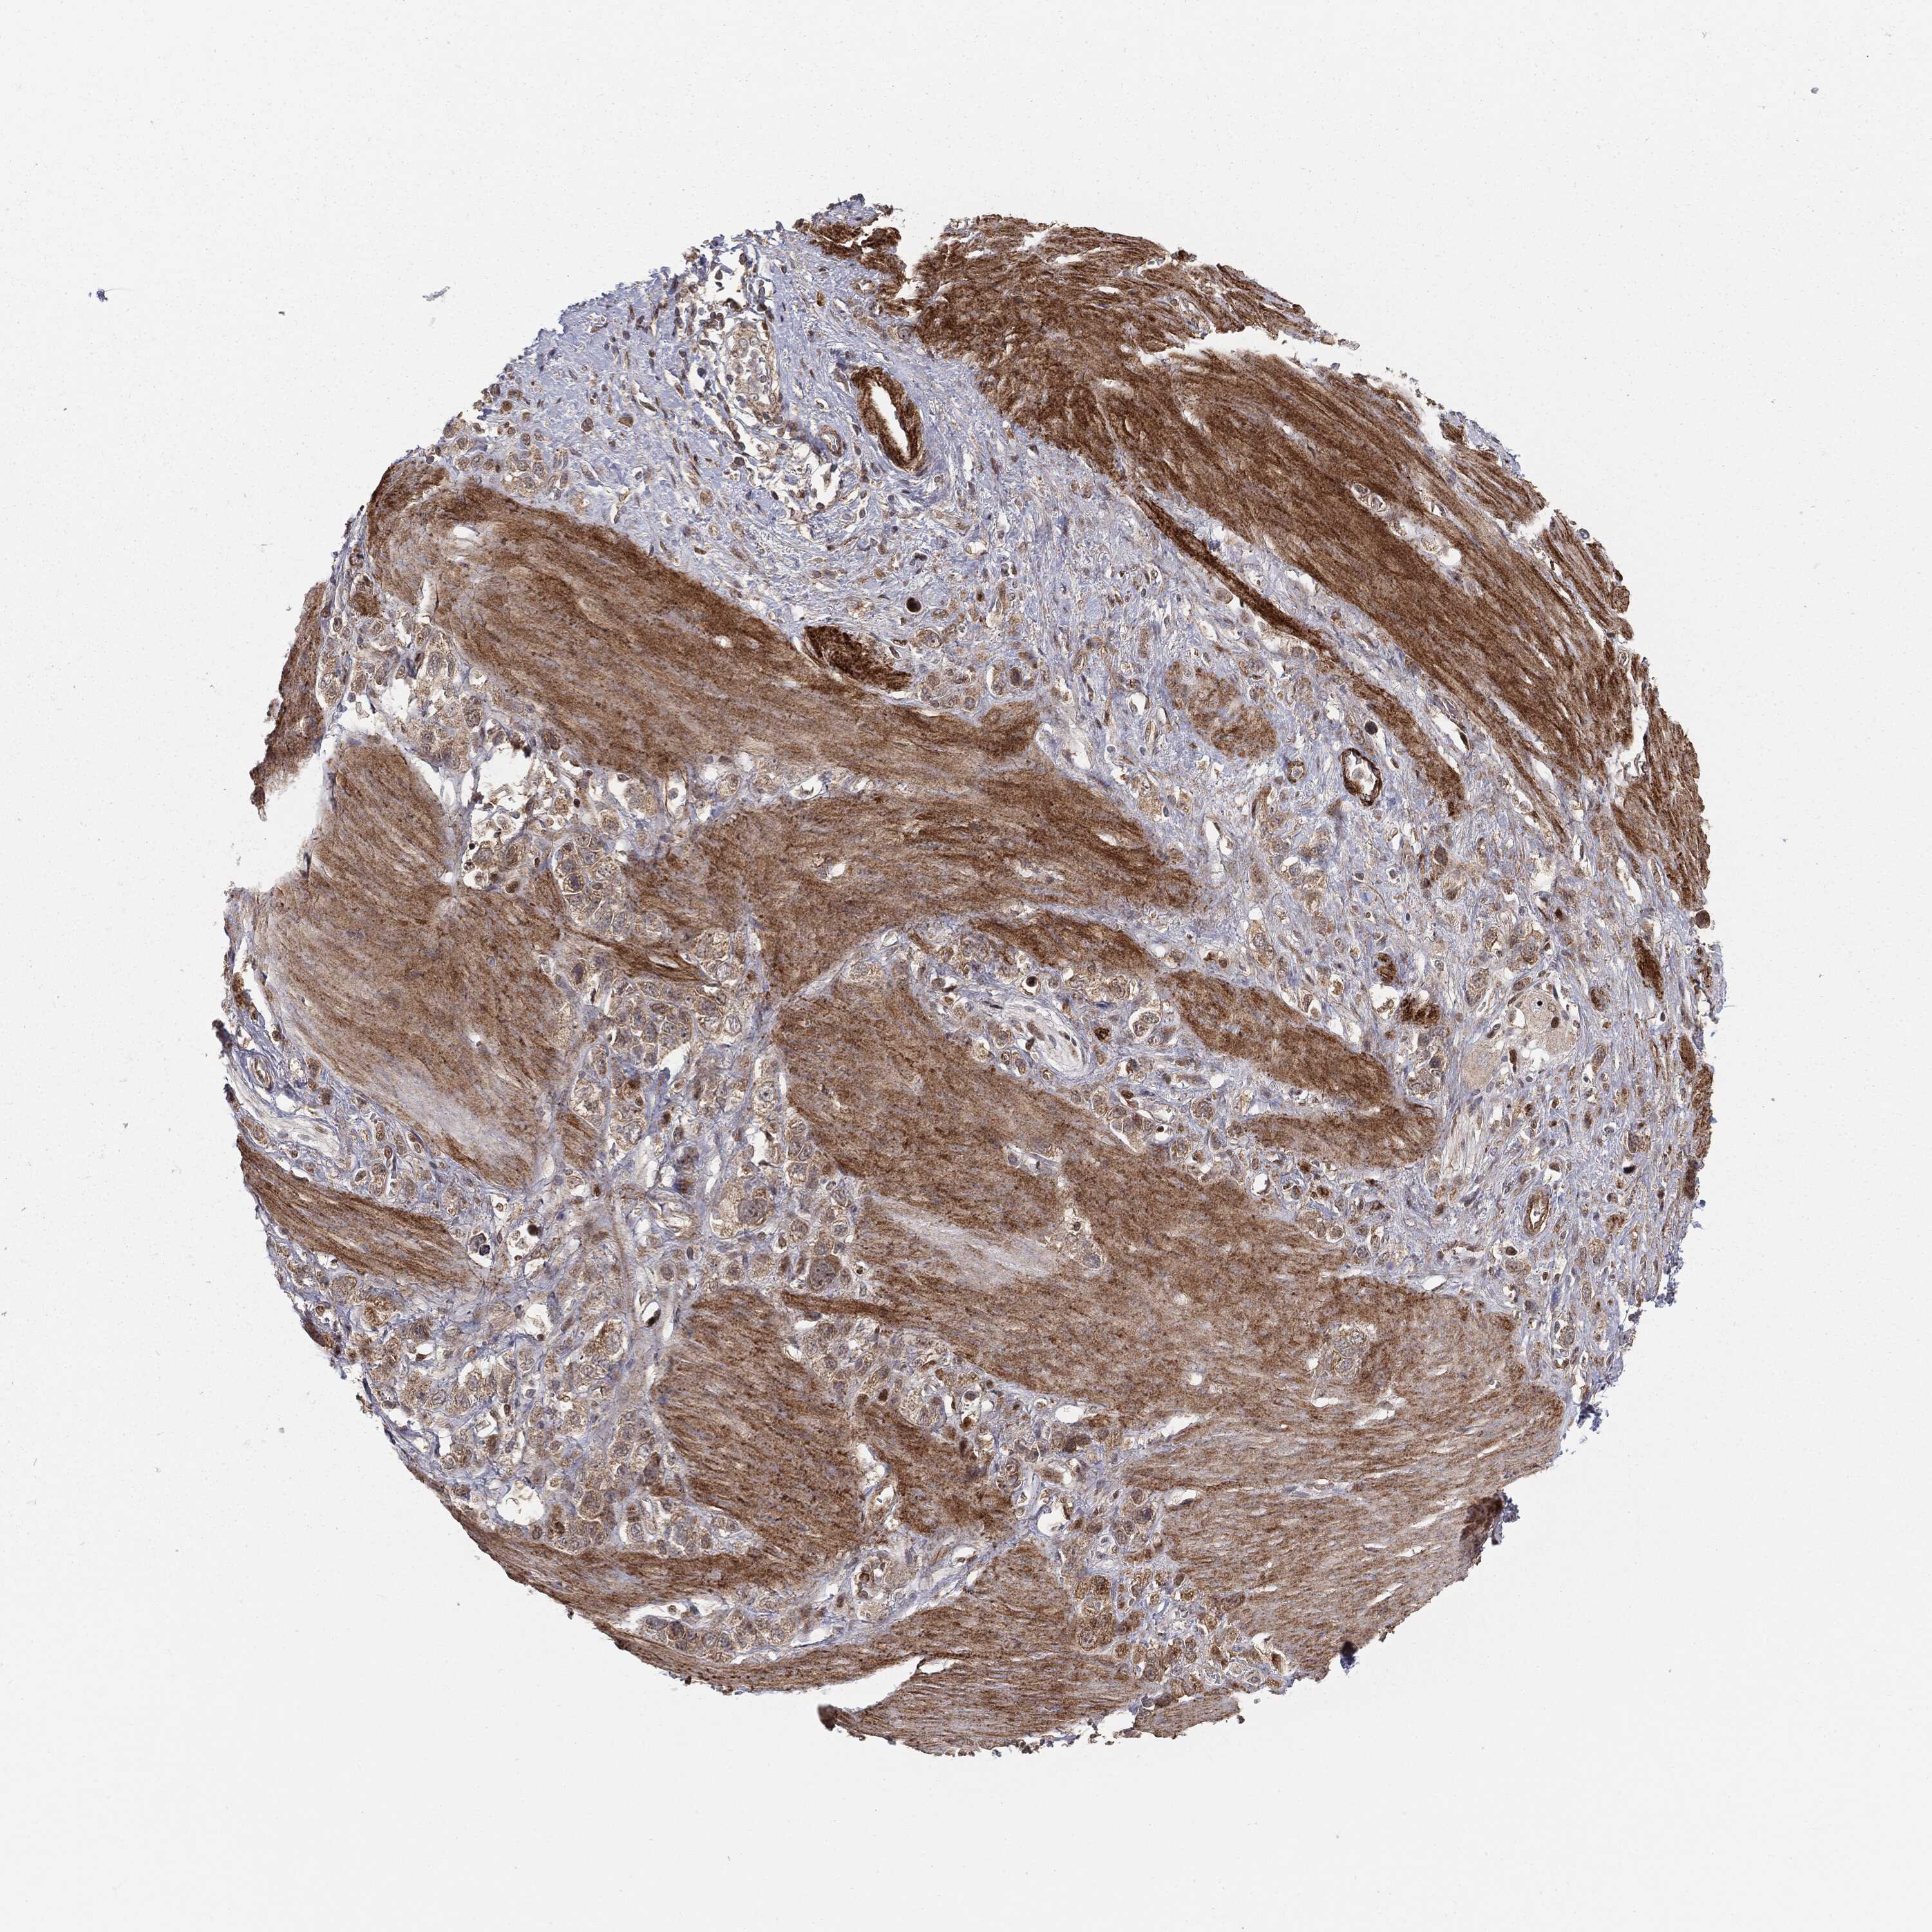

STOMACH CANCER - Protein expressioni

A mouse-over function shows sample information and annotation data. Click on an image to view it in a full screen mode. Samples can be filtered based on level of antibody staining by selecting one or several of the following categories: high, medium, low and not detected. The assay and annotation is described here.

Note that samples used for immunohistochemistry by the Human Protein Atlas do not correspond to samples in the TCGA dataset.

Antibody stainingi

Antibody staining in the annotated cell types in the current human tissue is reported as not detected, low, medium, or high, based on conventional immunohistochemistry profiling in selected tissues. This score is based on the combination of the staining intensity and fraction of stained cells.

Each image is clickable and will lead to virtual microscopy that enables deeper exploration of all samples and also displays staining intensity scores, fraction scores and subcellular localization as well as patient and tissue information for each sample.

Antibody HPA031335

Antibody CAB004076

Antibody CAB080153

Antibody CAB080157

Staining

High

Medium

Low

Not detected

Intensity

Strong

Moderate

Weak

Negative

Quantity

>75%

75%-25%

<25%

None

Location

Nuclear

Cytoplasmic/membranous

Cytoplasmic/membranous,nuclear

Adenocarcinoma, NOS

Adenocarcinoma, High grade